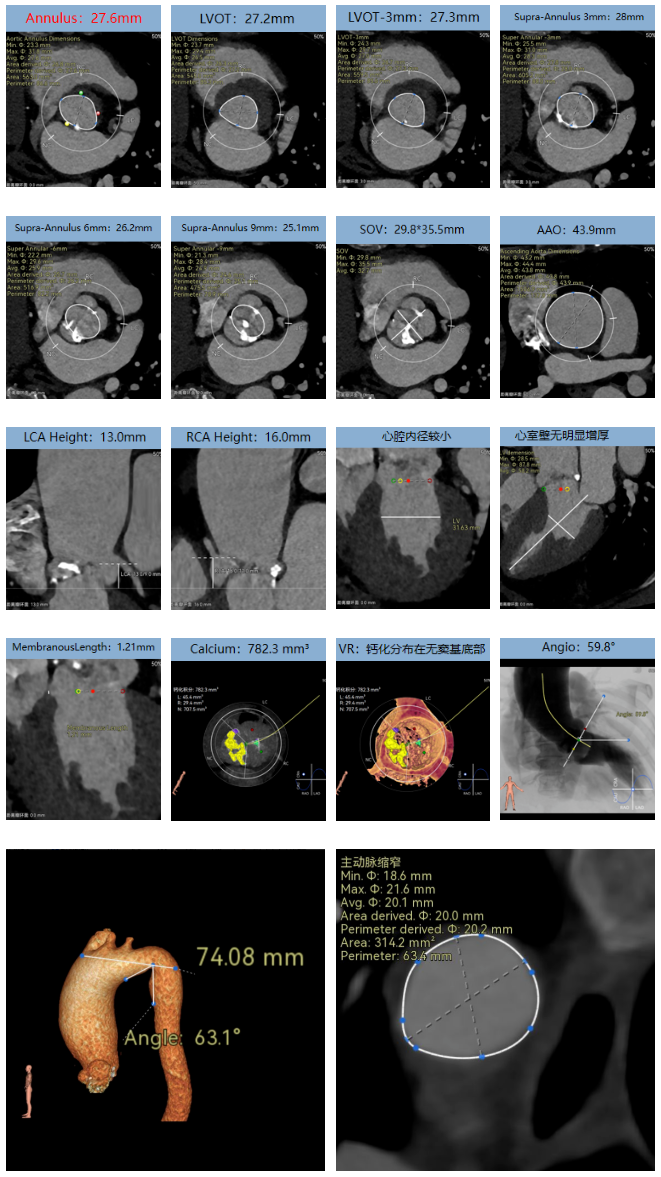

术前CT

Type1型(L-R)二叶瓣,瓣环径27.6mm,LVOT27.2mm,瓣上限制逐渐加重,火山口预估大小24mm,瓣上限制重;双侧冠脉开口高度可,瓣叶不长、窦部空间较大,无冠脉风险;重度钙化,钙化集中在无窦基底部及瓣叶边缘与L-R交界处,心脏角度59.8°;心腔内径可,心室壁无明显增厚,室间隔膜部较短,有一定PPI风险;外周入路无钙化、双侧入路无明显迂曲,左右股动脉内径可、中分叉,主动脉弓处有缩窄,弓距较短,过弓有一定难度。